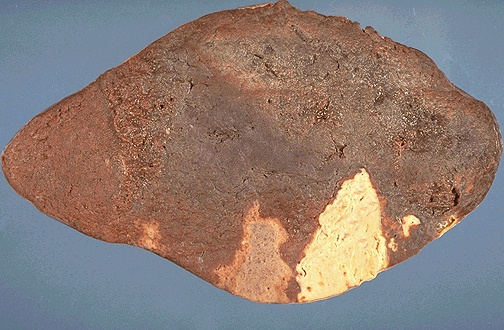

肾盂积水

hydronephrosis

1.肾脏体积增大

2.切面见肾盂肾盏扩张成囊状

3.肾实质受压高度萎缩